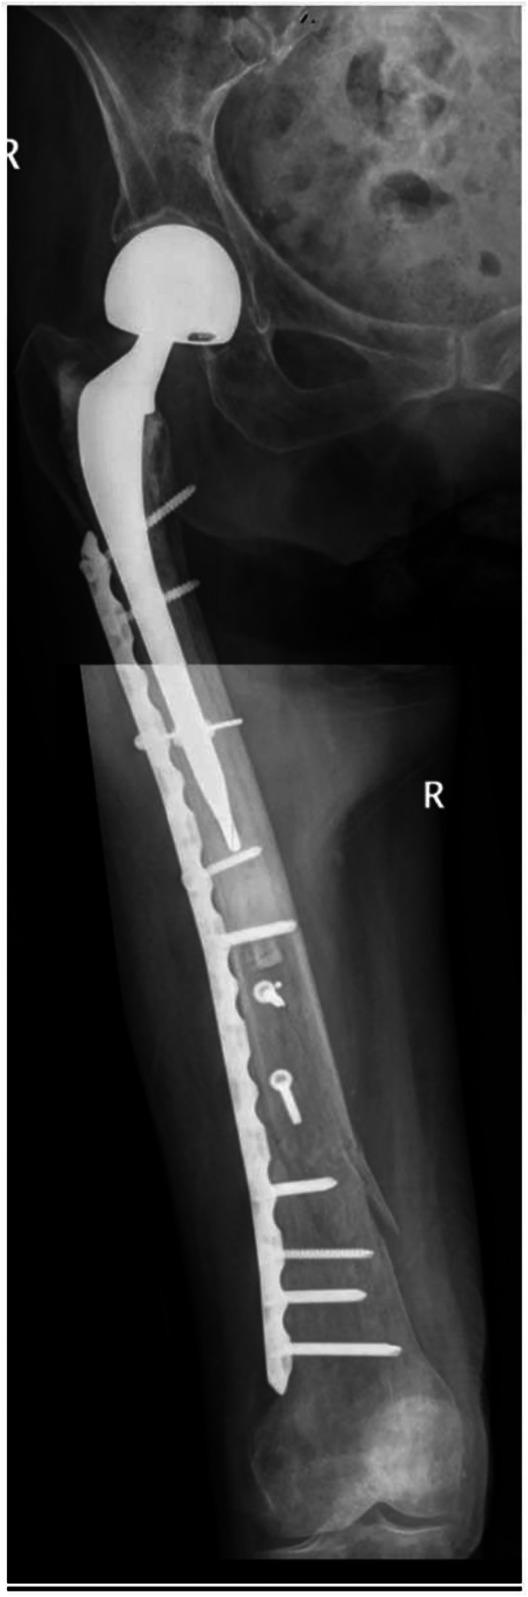

Periprosthetic fractures of the distal femur have significant morbidity in both total hip and total knee arthroplasty (THA and TKA, respectively). The incidence of these fractures is growing, with the predominant mechanism of injury being a fall from a standing height and therefore considered fragility fractures. In many countries, improved public funding and a flourishing private health care sector, when coupled with increased life expectancy, translates to more older patients receiving both TKA and THA and therefore an increased prevalence of periprosthetic fractures and their associated complications. These fractures may occur below a long stem THA, above a TKA, or between the two (so-called "interprosthetic fracture"). We will outline fracture classification, risk factors, diagnosis, and treatment options, highlighting perspectives on treating these fractures in Israel, South Africa, and South Sudan. These countries represent differing access to resources, varied comorbidity factors, and differing health care systems. The points of difference and the points of similarity will be considered.

股骨远端假体周围骨折在全髋关节置换术和全膝关节置换术(分别为THA和TKA)中均具有较高的发病率。这些骨折的发生率正在上升,主要损伤机制是从站立高度跌落,因此被视为脆性骨折。在许多国家,公共资金的改善和蓬勃发展的私立医疗保健部门,再加上预期寿命的延长,意味着更多老年患者接受TKA和THA,从而导致假体周围骨折及其相关并发症的患病率增加。这些骨折可能发生在长柄THA下方、TKA上方或两者之间(所谓的“假体间骨折”)。我们将概述骨折分类、危险因素、诊断和治疗选择,重点介绍以色列、南非和南苏丹治疗这些骨折的观点。这些国家代表了不同的资源获取情况、不同的合并症因素和不同的医疗保健系统。将考虑差异点和相似点。